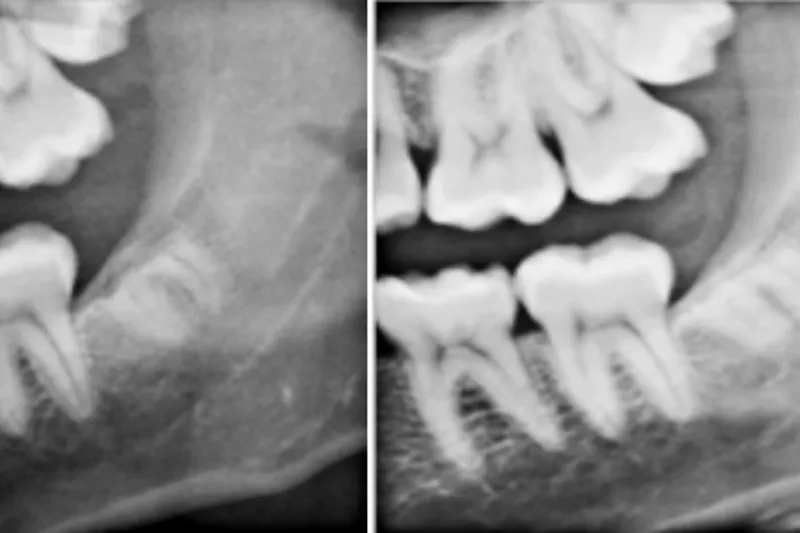

I undersøgelsen blev 231 rodkomplekser fulgt klinisk og radiologisk i gennemsnitlig 5,7 år efter koronektomi. Koronektomi blev valgt frem for fjernelse af hele tanden, fordi der på CBCT blev påvist en tæt relation mellem rodkomplekset og canalis mandibularis.

I alt blev der konstateret 37 tilfælde af postoperative komplikationer (16,0 %), hvoraf de fleste var infektioner, som kunne behandles med antibiotikum. Prævalensen af nerveskader på n. alvolaris inferior var 1,3 % (tre tilfælde af lettere føleforstyrrelser), og 3,5 % af de efterladte rødder måtte fjernes på et senere tidspunkt, primært fordi de vandrede og brød igennem mundslimhinden.